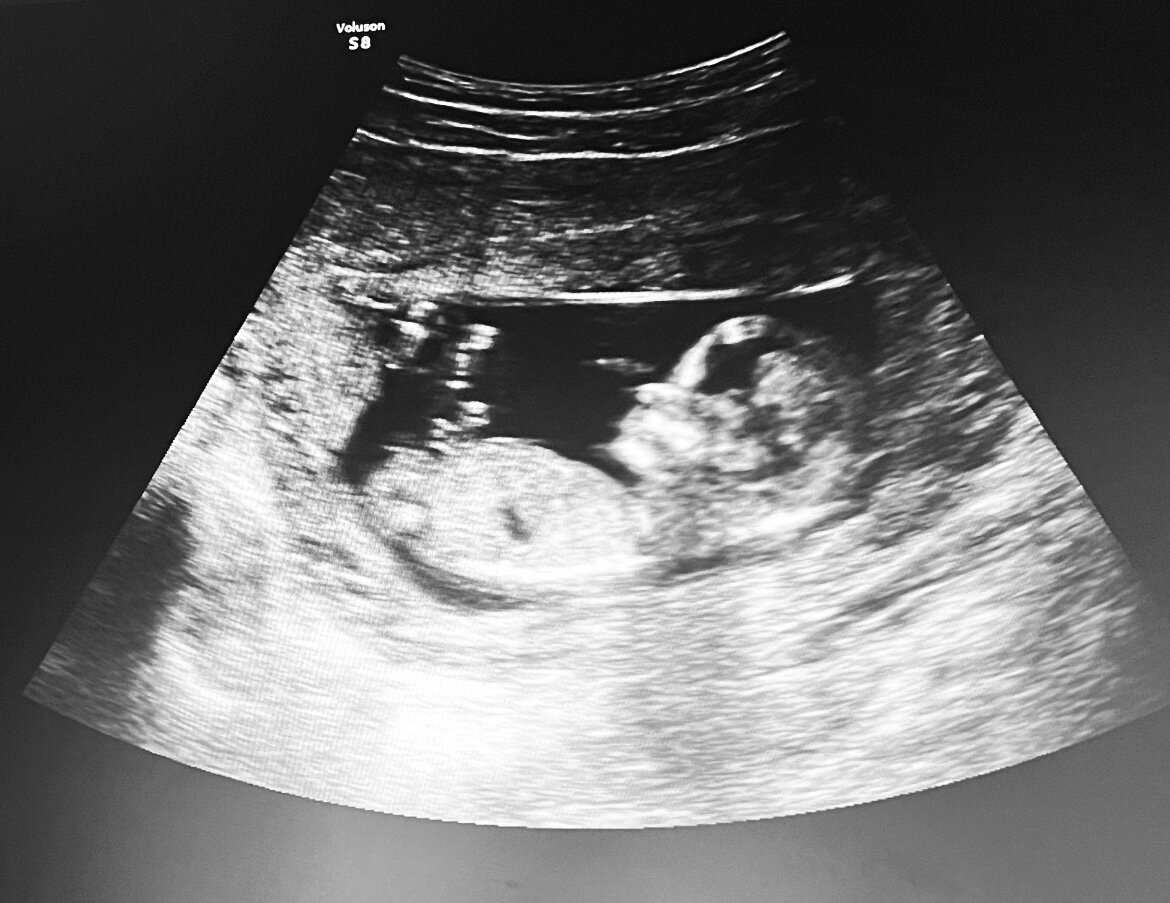

Пренатальные скрининги во время беременности являются важным и неотъемлемым аспектом современной акушерской практики. Эти проверки, проводимые врачами на протяжении всего периода беременности, позволяют выявить различные заболевания и аномалии у плода еще до его рождения.

Зачем они нужны? Прежде всего, пренатальные скрининги позволяют выявить такие врожденные патологии, как Даун-синдром, спинальная грыжа, врожденные пороки сердца и другие серьезные заболевания. Это дает возможность родителям получить дополнительную информацию о состоянии и здоровье их будущего ребенка. Таким образом, родители могут быть готовы к возможным осложнениям, принять осмысленные решения в отношении родов и обеспечить своему ребенку лучшую заботу и поддержку.

Также пренатальные скрининги могут помочь выявить различные аномалии в развитии плода, такие как отклонения в росте и развитии органов. Это позволяет врачу принимать своевременные меры для предотвращения возможных осложнений и назначать необходимое лечение или медицинские процедуры.

Пренатальные скрининги также играют важную роль в определении состояния и здоровья матери. Они позволяют выявить такие заболевания, как преэклампсия (гестоз) и диабет, которые могут оказать негативное влияние на беременность. Благодаря скринингам врачи могут предпринять необходимые меры для поддержания здоровья матери и защиты ее и ребенка от возможных осложнений.

Важно отметить, что пренатальные скрининги являются почти безопасными и неприятными процедурами. Большинство из них не наносят вреда ни матери, ни ребенку. Это включает в себя ультразвуковые исследования, анализ крови и амниоцентез (исследование амниотической жидкости). Однако, перед проведением любых процедур, врач должен сообщить родителям о возможных рисках и необходимости согласия.